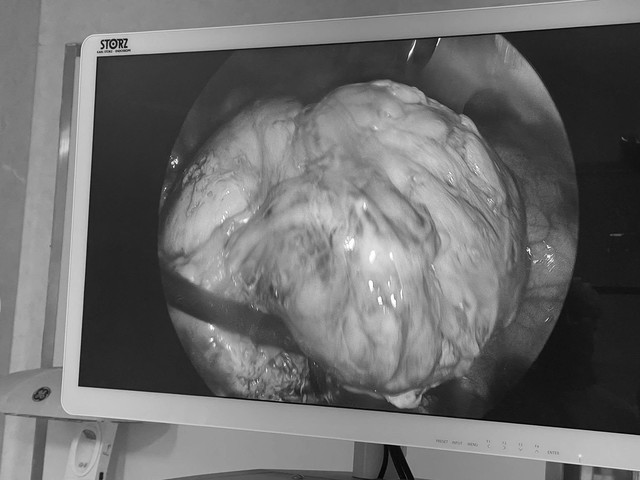

Siêu âm ghi nhận người bệnh có khối u kích thước 102x80mm. Ảnh: BVCC

Trong quá trình phẫu thuật, ê-kíp phải đối mặt với nhiều khó khăn: khối u lớn nằm ở thành sau tử cung, nguy cơ chảy máu cao, đặc biệt trên nền bệnh nhân thiếu máu nặng và có sẹo mổ cũ.

Tuy nhiên, bằng kinh nghiệm và kỹ thuật chuyên sâu, các bác sĩ đã bóc tách thành công khối u qua nội soi, kiểm soát tốt lượng máu mất và bảo tồn nguyên vẹn tử cung.